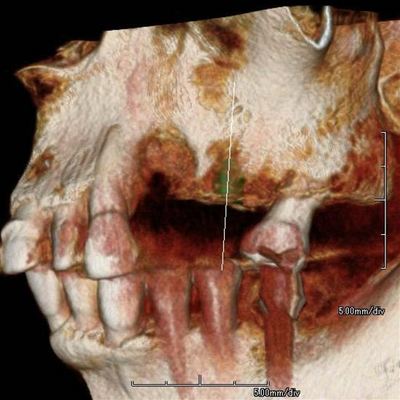

左上臼歯部のCT画像です。

2本の埋入計画を立てますが第一小臼歯部分に骨欠損があります。